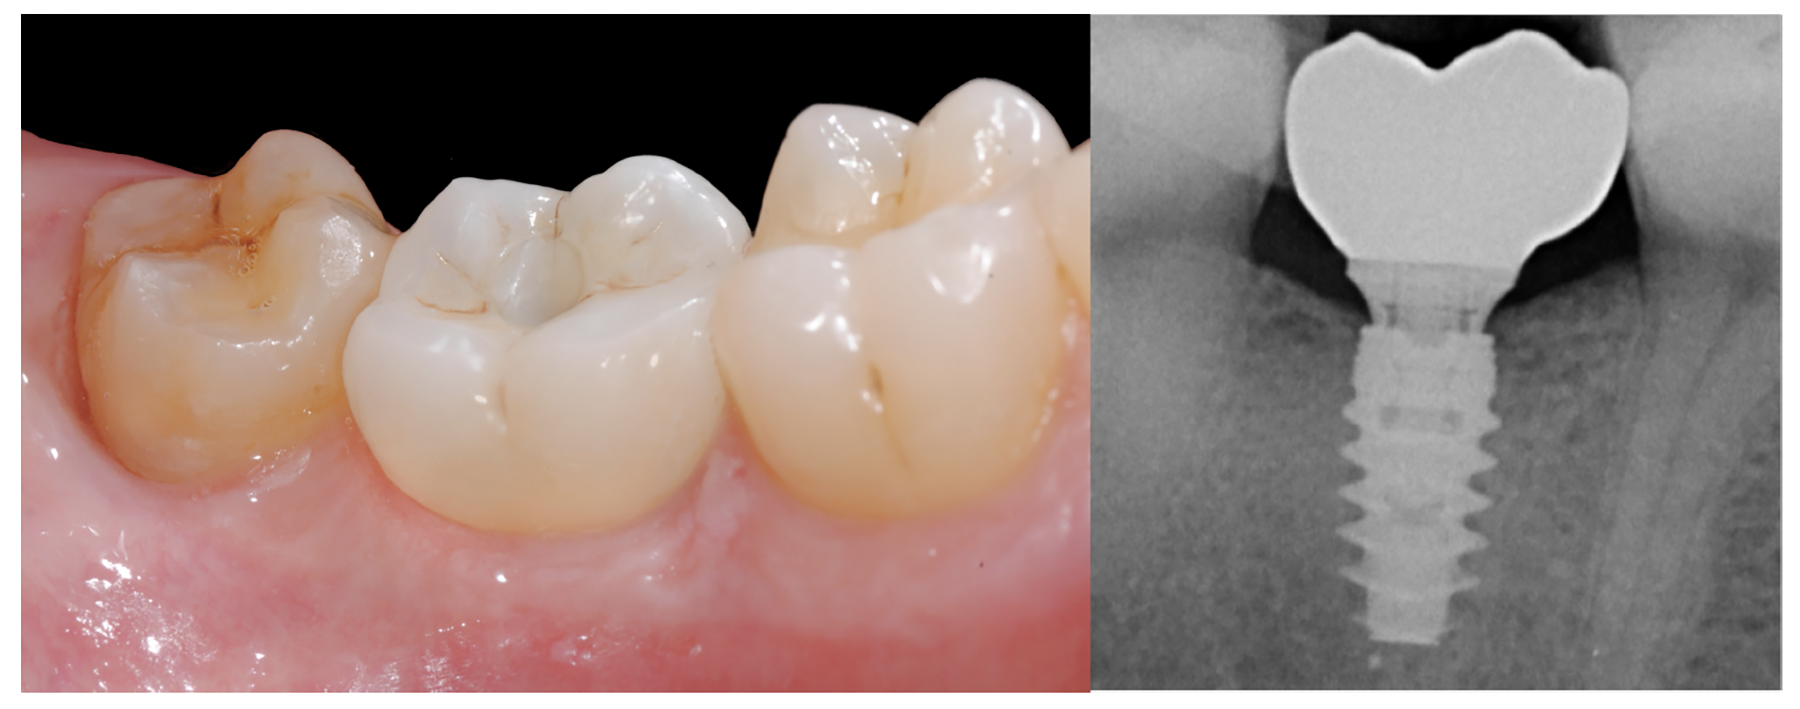

Finally, once the proper 3D position of the implants has been identified, the abutment placement protocol to be used should be evaluated. The "one abutment/one time" approach4,6,8,17 allows soft tissues to adhere firmly onto the surface of titanium abutments, thereby improving soft tissue response and bone stability (Figure 4 and Figure 7 through Figure 14 ). This approach avoids multiple connections and disconnections at the bone interface and favors undisturbed bone and soft tissue healing.4-7

Fig. 10